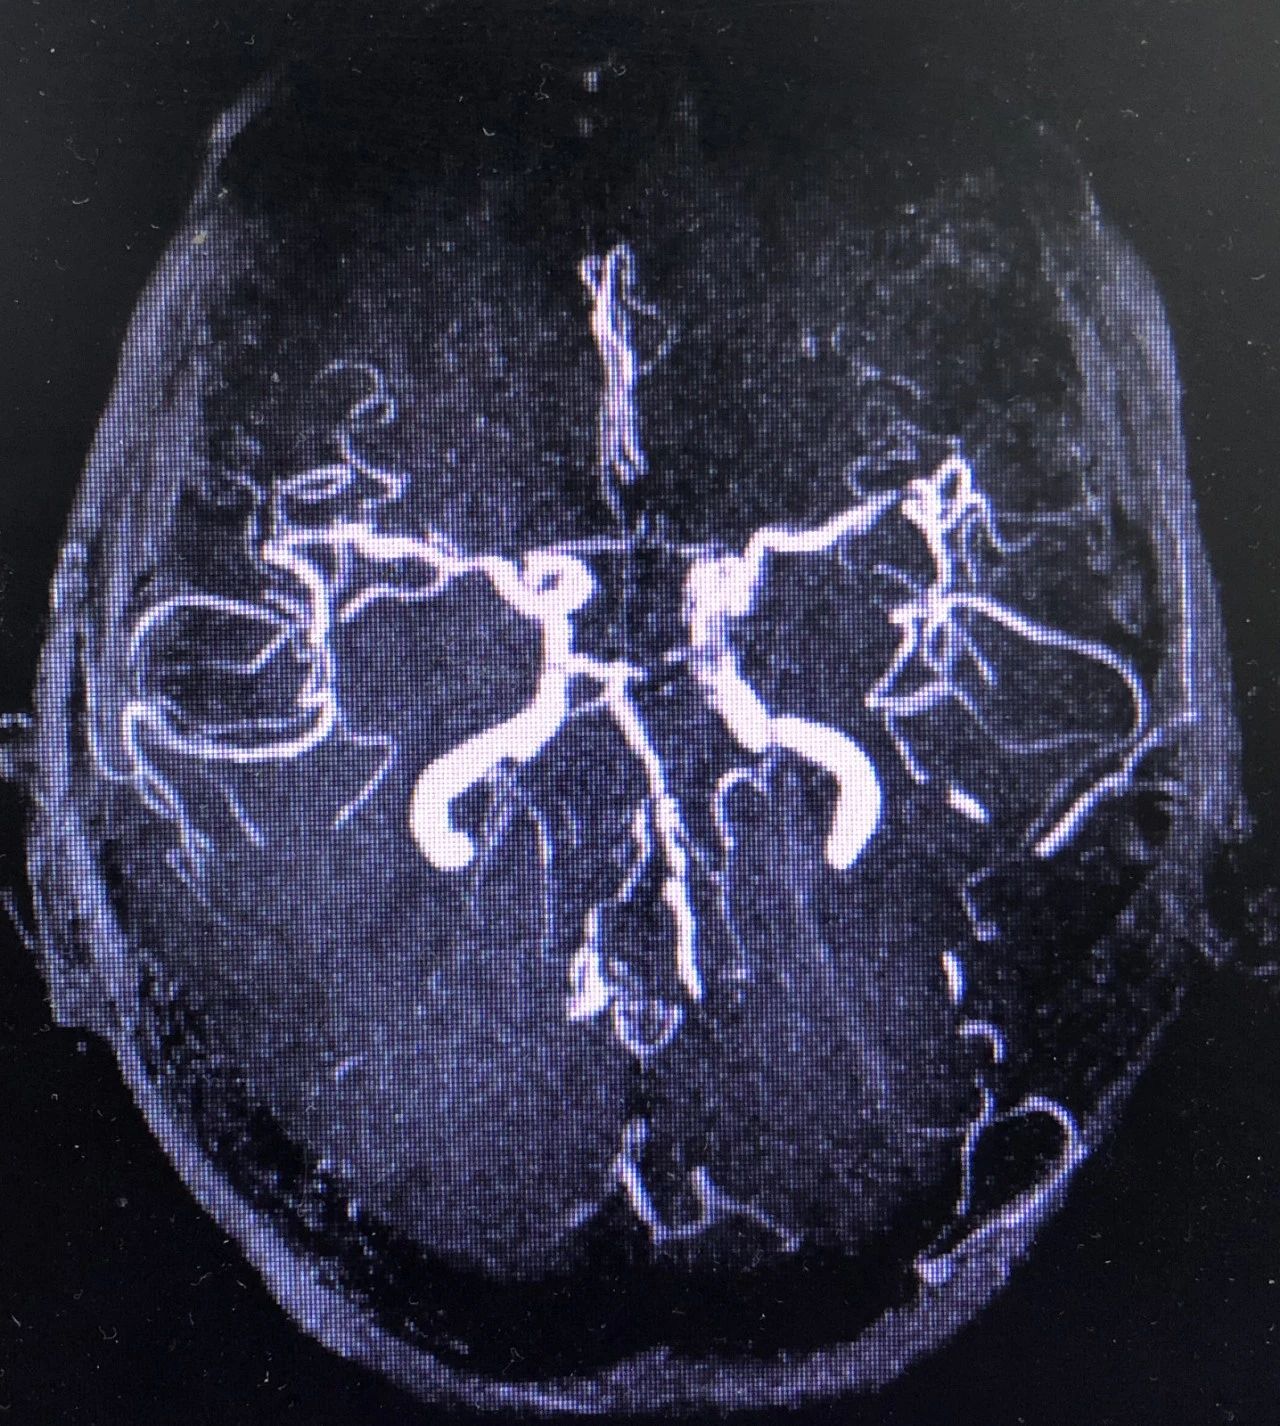

辅助检查:12导联心电图示:窦性心律;头颅MRI示:双侧小脑半球多发斑片状急性期脑梗死,椎、基底动脉多发狭窄。

MRA

依据脑梗死分型,当时考虑大动脉粥样硬化型,但是很奇怪为什么双侧小脑半球都有病灶,难道还有其他病因?碰巧的是患者在院期间诉心慌,就再次给予复查了心电图,如下: